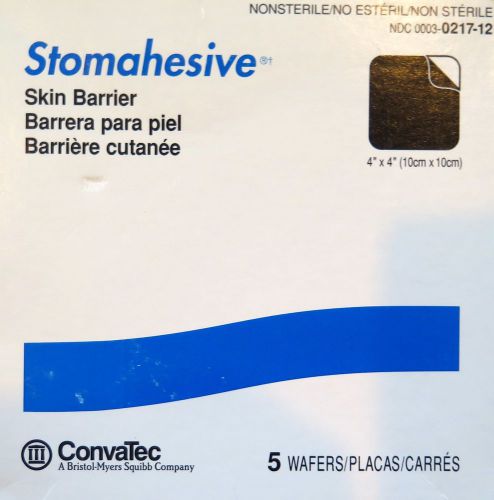

Convatec Stomahesive Skin Barrier Wafers 4" X4"-ref 0217-12-lot of 5